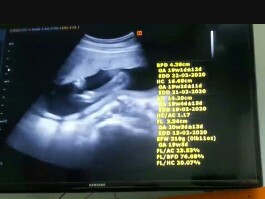

สามารถได้เห็นเพศ ลูกน้อยตอนกี่เดือนบ้างคะ

ขอความคิดเห็นของคุณแม่ๆหน่อยค้า